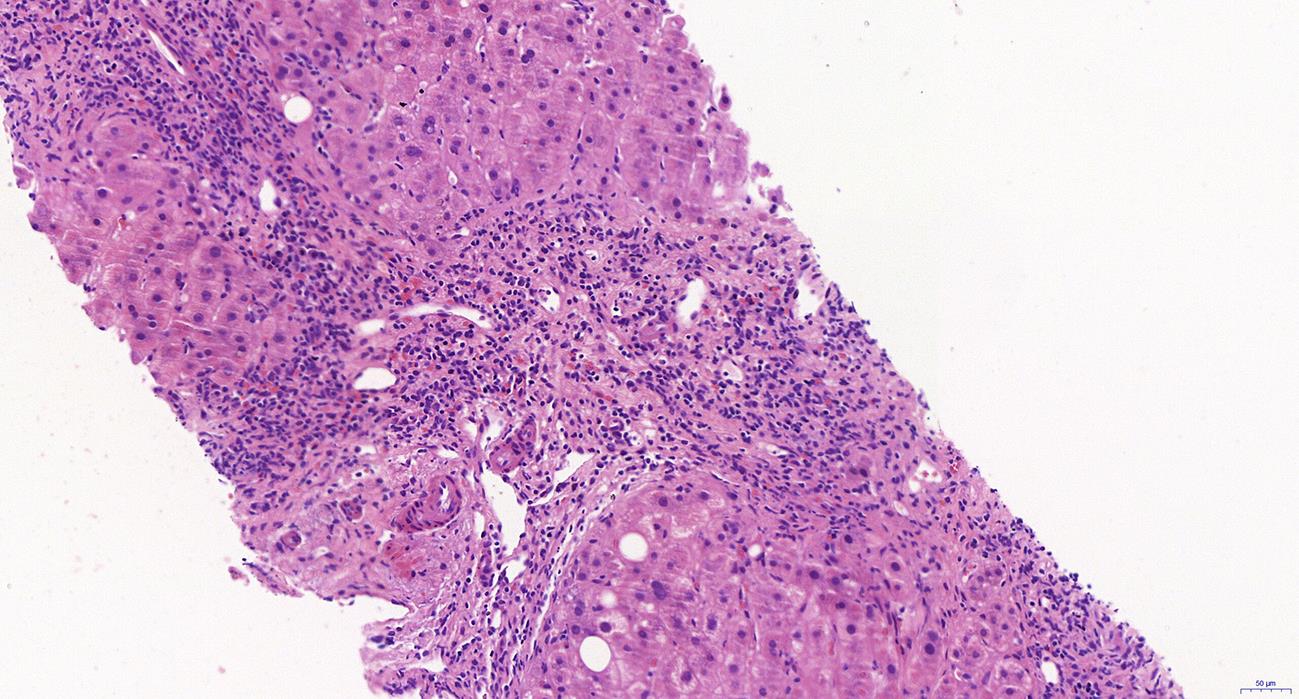

自身免疫性胰腺炎(AIP)是一种少见疾病,其诊断应基于对临床、影像学、血清学和病理学结果全面评估。目前将AIP分为两型:1型AIP被认为是与IgG4相关疾病的胰腺表现;2型AIP被视为与IgG4无关的胰腺特异性疾病。尽管1型和2型AIP的发病机制似乎不同,但二者的影像学表现相似,且均对类固醇激素有良好反应。本综述主要关注于AIP 2个亚型的病理组织学特征,尤其是内镜超声引导的细针穿刺活检组织的病理诊断难点,以提高AIP临床诊断的准确性。